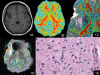

We evaluate the value of MR diffusion tensor imaging (DTI) and dynamic susceptibility-weighted contrast material-enhanced perfusion-weighted imaging (PWI) in preoperative grading of supratentorial nonenhancing gliomas. This institutional review board-approved, Health Insurance Portability and Accountability Act-compliant retrospective study involved 52 patients: 37 with low-grade gliomas (LGGs) and 15 with high-grade gliomas (HGGs). The mean trace apparent diffusion coefficient (ADC), minimal ADC, mean fractional anisotropy (FA), maximal FA, and maximal relative cerebral blood volume (rCBV) ratio of the lesions were measured and compared between LGG and HGG. The efficacy of the above parameters in grading supratentorial nonenhancing gliomas was evaluated. There was no significant difference in rCBV ratio, minimal ADC, and mean ADC between LGG and HGG (p > 0.05). The mean and maximal FA values of LGG were significantly lower than the values of HGG (p < 0.001). The receiver operating characteristic analysis showed that the mean FA with a cutoff value of 0.129 and the maximal FA with a cutoff value of 0.219 could differentiate between LGG and HGG with specificity of 69.2% and 76.9%, respectively, and sensitivity of 93.3% and 100.0%, respectively. The combination of mean FA and maximal FA based on the linear discriminant analysis improved the diagnostic accuracy with specificity of 92.3% and sensitivity of 86.7%. These findings were better than maximal rCBV ratio, mean ADC, and minimum ADC. The mean FA and maximal FA, used individually or combined, may be useful in preoperative grading of supratentorial nonenhancing gliomas.